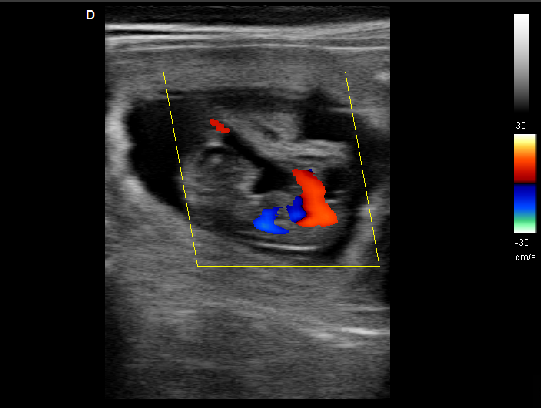

P5-VET獸用彩超機(jī)脊椎檢查圖

脊椎檢查:

脊柱裂的預(yù)防和確診,一般在動(dòng)物懷孕以后定期給動(dòng)物做超聲檢查,通過(guò)超聲、超聲檢查可以早期發(fā)現(xiàn)動(dòng)物胎兒是否合并了脊柱裂或是神經(jīng)管閉合不全。